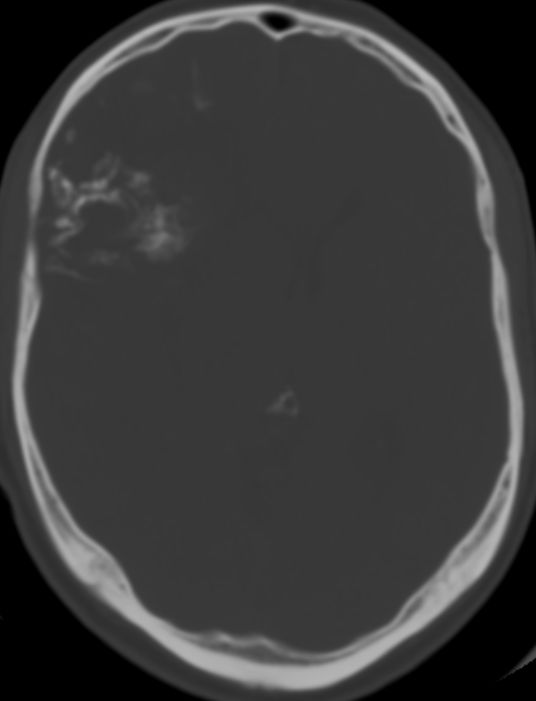

CT

46-jähriger Mann mit anaplastischem Oligodendrogliom WHO-Grad III rechts fronto- parieto-temporal, keine 1p19q-Deletion, IDH-1-Mutation, Ki67 12%.

Der Patient erlitt beim Autofahren einen epileptischen Anfall mit Myoklonien des gesamten Körper und Bewusstlosigkeit.